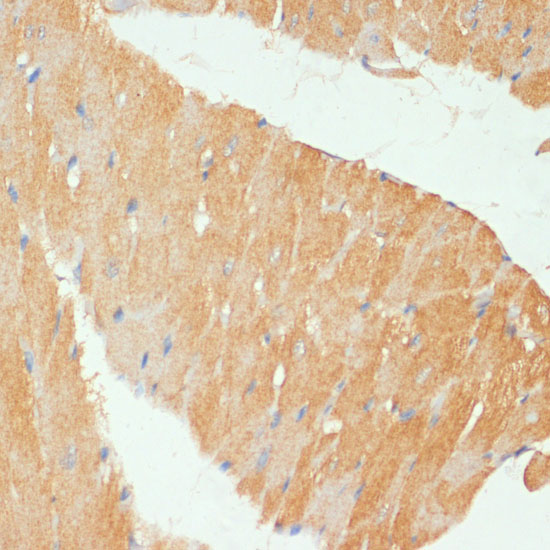

Immunohistochemistry of paraffin-embedded rat heart using MYBPC3 at dilution of 1:100 (40x lens).

Immunohistochemistry of paraffin-embedded mouse heart using MYBPC3 at dilution of 1:100 (40x lens).